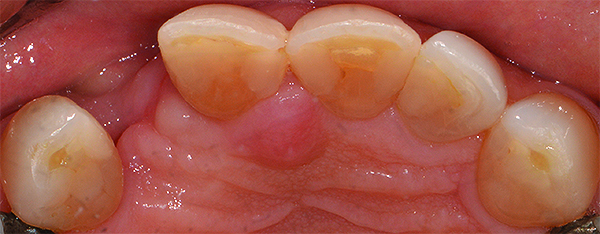

(1.) Optical scan of a maxillary arch (occlusal view). The impression provides details that allow the dentist to visualize composite and amalgam restorations, a fractured lingual cusp on the second maxillary left premolar, a metal ceramic crown on the maxillary right first molar, and an implant-supported anterior fixed dental prosthesis.

Figure 1